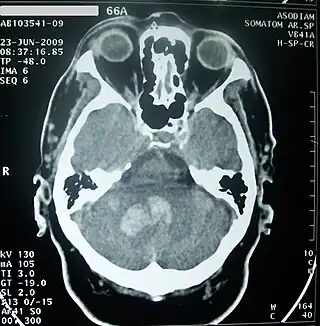

![]() | ||

![]() Cerebelo en púrpura. Sección sagital de un encéfalo en una RMN. | ||